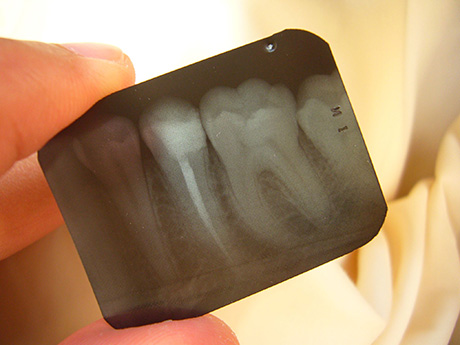

This procedure becomes necessary when the tooth pulp becomes infected, which is usually caused by tooth decay. The roots become filled up with bacteria, and they stick to the inside of the tooth chamber as well. During the procedure the infected pulp along with parts of the wall are removed. The roots are then filled with an antibiotic filling, and sealed. If needed, the tooth will also be crowned.

Often enough the tooth will not hurt, but will be infected enough that it does actually need a root canal treatment. There are several methods that doctors can use to see if the inside of the tooth is infected, and if it is, regardless of pain, a root canal treatment will become necessary. Keep an eye out for preliminary signs; like if there are any sudden, small growths around the tooth (these are fistulas), as these necessarily imply an infection. These tiny bumps can disappear, but that does not mean that the problem is solved. If you feel these tiny bumps, go and see a dentist immediately.